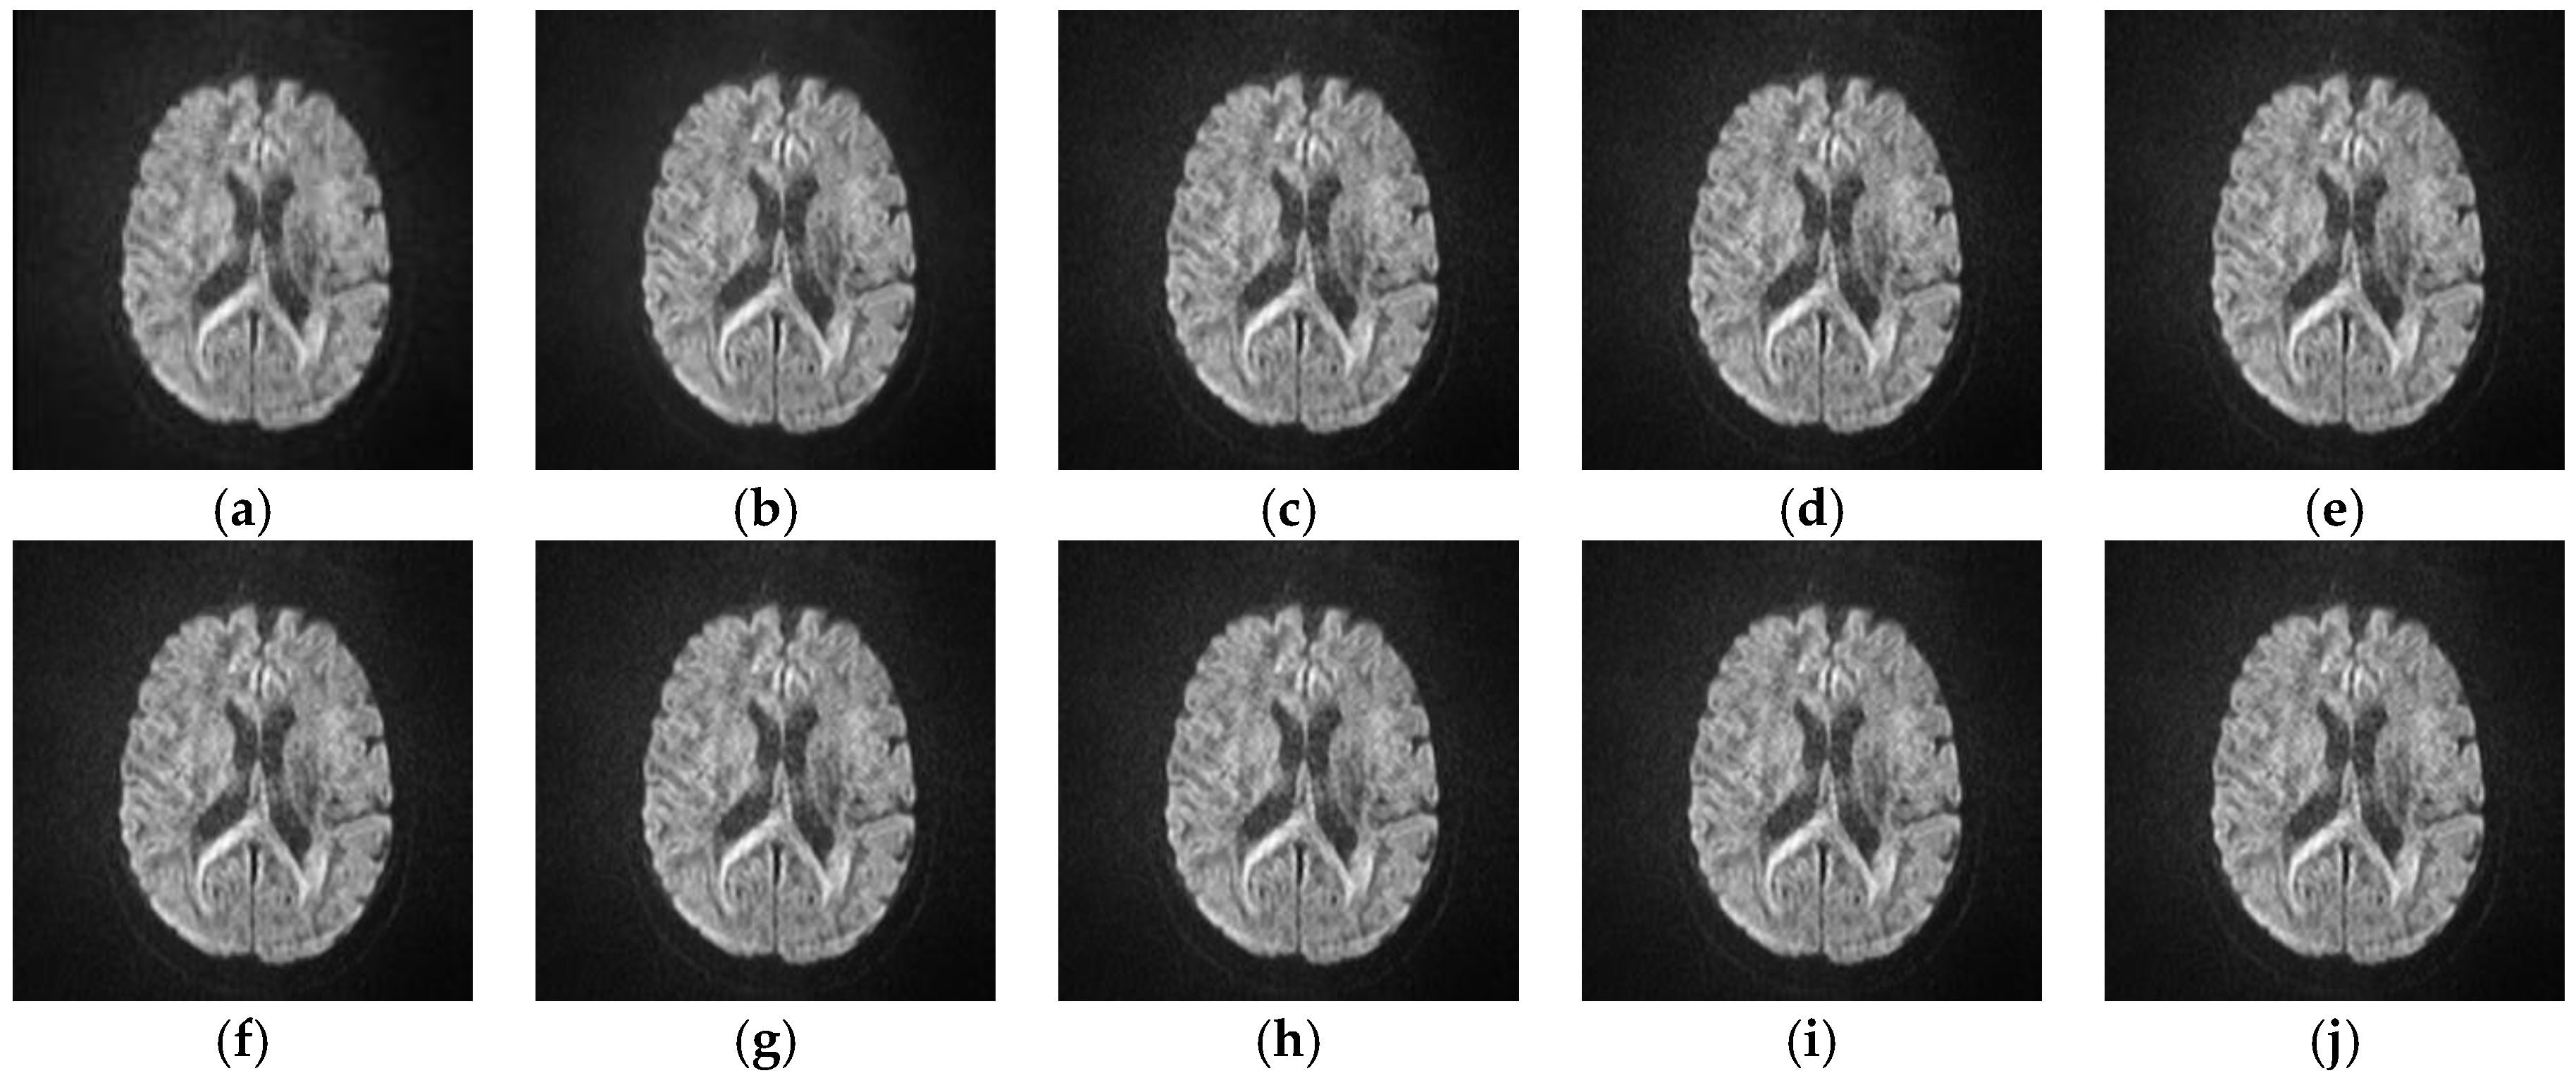

5.2.4. Analyze the Performance of Different SR Algorithms on Real Medical Images

| Indices | L1SR | SISR | ANR | NE + LS | NE + NNLS | NE + LLE | A + (16 Atoms) | ISPSR | SRISAE |

|---|---|---|---|---|---|---|---|---|---|

| Variance | 2446.8651 | 2479.3577 | 2483.4034 | 2480.6194 | 2478.4239 | 2481.2642 | 2483.7900 | 2483.0294 | 2486.2215 |

| Meangradient | 2.8012 | 3.2414 | 3.4120 | 3.2862 | 3.2877 | 3.4117 | 3.4927 | 3.4435 | 3.5033 |

| Entropy | 6.4871 | 6.5141 | 6.5256 | 6.5180 | 6.5170 | 6.5268 | 6.5275 | 6.5231 | 6.5383 |

| Brenner | 4,596,865 | 5,243,693 | 5,568,487 | 5,273,747 | 5,292,623 | 5,457,148 | 5,776,475 | 5,863,142 | 5,914,784 |

| Energy | 4,167,251 | 4,369,326 | 4,644,846 | 4,526,663 | 4,532,565 | 4,544,087 | 4,981,985 | 4,986,970 | 5,098,674 |